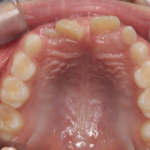

反対咬合(受け口)の症例

Before After 治療途中の小児矯正の症例です。 成長期に上顎の幅を広げ ...